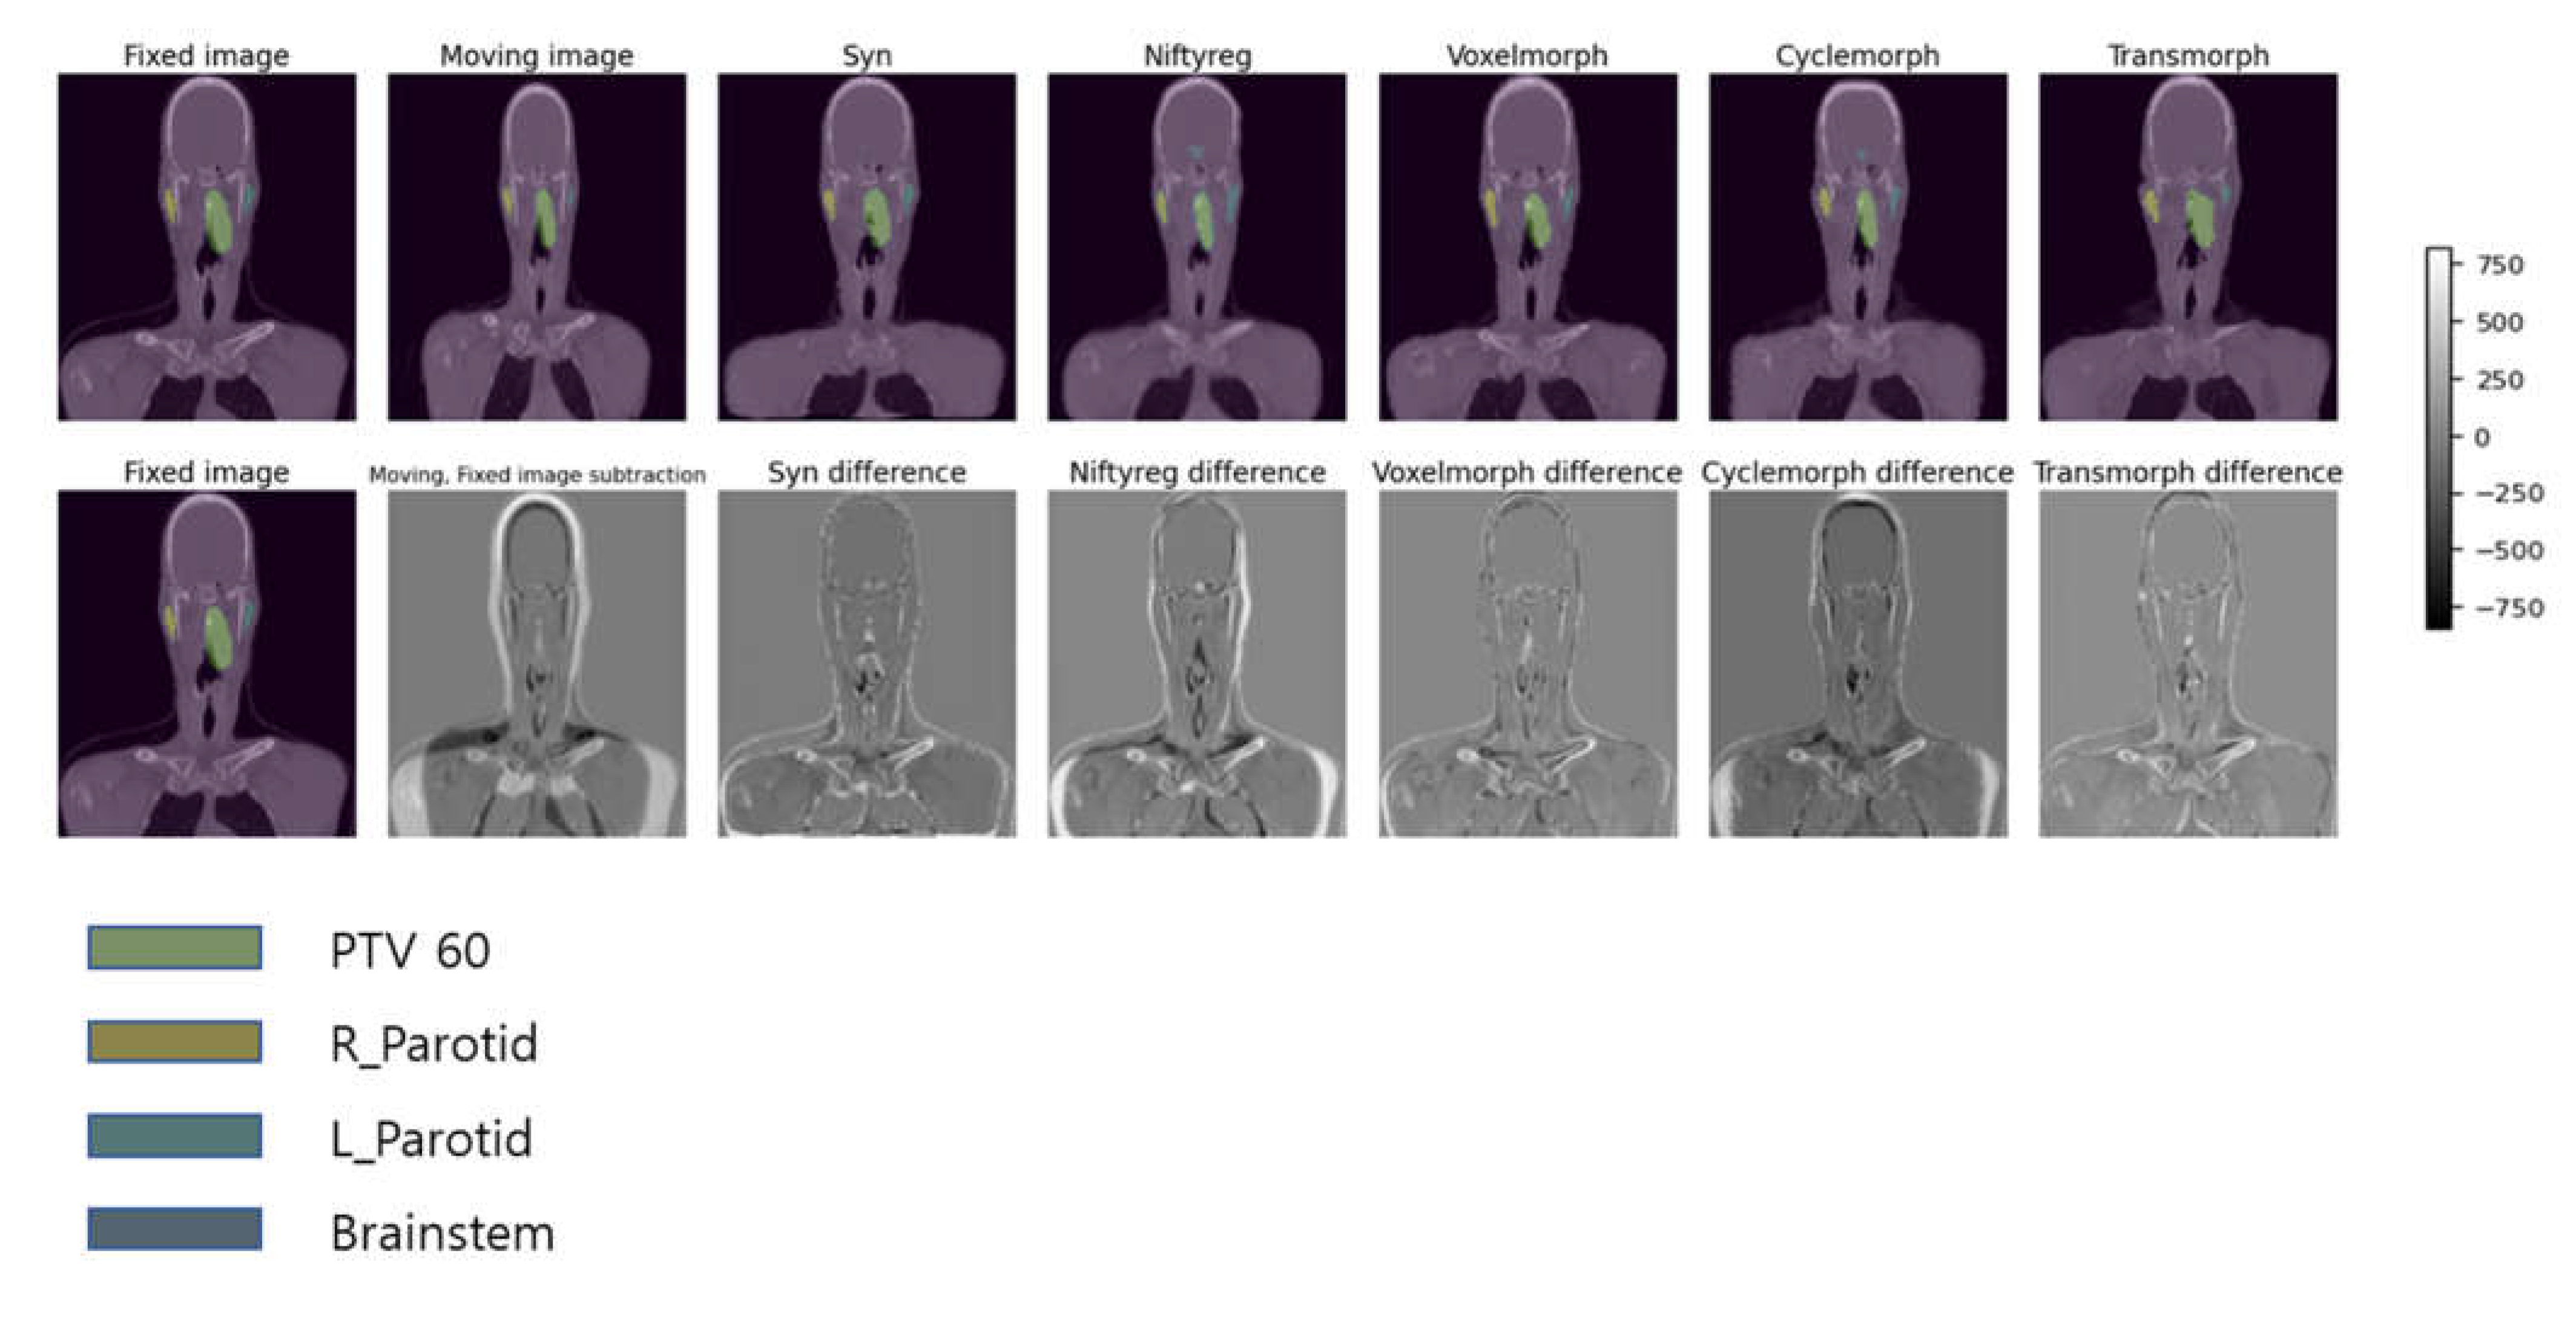

In Figure 3, we present examples of deformed images obtained using five different DIR algorithms along with their difference maps as compared to the original fixed image. Based on qualitative analysis, it can be concluded that the SyN and Transmorph algorithms produced reasonably accurate deformations, while the other algorithms showed relatively greater discrepancies from the moving image. Among these models, the best-deformed model was SyN (patient mean dice score: 0.76), which was well-deformed in the modified patient’s contour, airway, lung, and bone. The deformed images of SyN and Transmorph accurately denoted the heart between the moving image and the fixed image.

Figure 3. Pre-treatment to Mid-treatment image and contour propagation, example of deformed images based on 5 deformable image registration (DIR) algorithms in each OAR and PTV. The first row shows the deformed by each DIR algorithms in moving images and contours, and second row shows difference between deformed images.